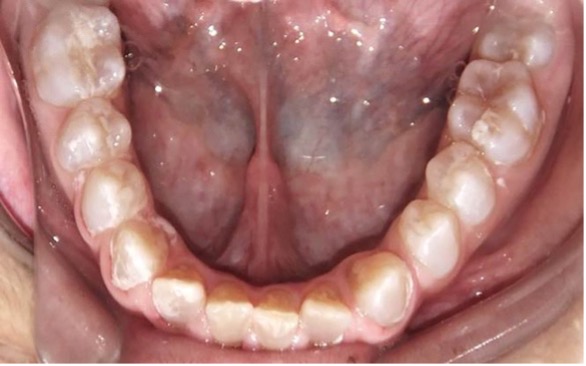

En la radiografía panorámica de control del año 2015 se observó la progresiva obliteración del conducto radicular en el grupo incisivo superior e inferior y en los primeros molares permanentes; presentado los premolares en erupción, un conducto radicular anormalmente amplio en toda su longitud (Figura 8). En la del año 2018 se visualizó la continua aposición de dentina a nivel radicular que obliteró en forma casi total los conductos de la mayoría de las piezas dentarias, a excepción de los segundos molares inferiores (Figura 10).

Figura 10: Rx panorámica 2018.

Figura 11: Controles clínicos 2018

En el último control realizado en el año 2018 (Figura 11) el paciente mantuvo el estado de salud logrado. El análisis cariogénico fue moderado (por su historia pasada de caries y su condición biológica específica) y el gingivoperiodontal bajo. El paciente continúa en atención en la COIN. Fue derivado en varias oportunidades al servicio de Ortodoncia de la Facultad de Odontología de la Universidad de Buenos Aires, pero hasta el momento no encaró ningún tratamiento propuesto.